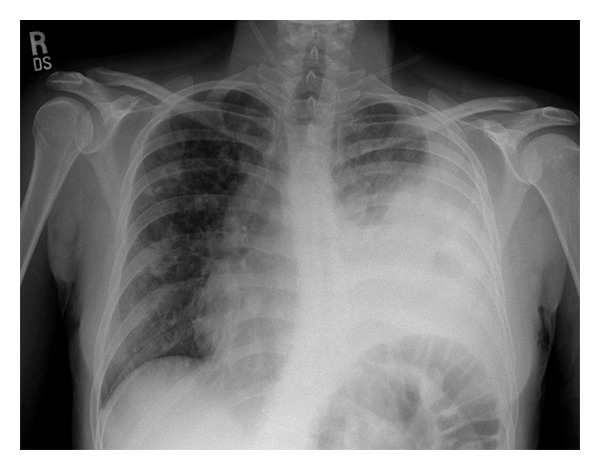

Input 2: What is seen in the X-ray and what should be done? ![]()

Visual input constitutes a vital component of the medical domain, supplying indispensable information in healthcare environments. Healthcare professionals extensively depend on visual cues for diagnosis, monitoring, and treatment of patients. Medical imaging technologies, such as X-rays, CT scans, and MRIs, offer unparalleled insight into internal organs, detecting diseases and abnormalities that may be invisible to the naked eye. Additionally, scientific figures and medical records, including plots, charts, and tables, are prevalent in the medical field. We propose linking visual experts with Med-Alpaca, as foundation model chaining presents a modular and highly adaptable framework for incorporating a diverse array of visual modules. Within this framework, any multimodal task can be divided into two essential stages: (1) the conversion of images to text, and (2) cognitive reasoning based on the derived text. In our context, visual experts (i.e., visual foundation models) transform medical images into an intermediate text representation. This converted data is then used to prompt a pretrained LLM, leveraging the inherent few-shot reasoning capabilities of LLMs to generate appropriate responses. Currently, our platform supports two distinct visual experts: Med-GIT and DePlot, chosen due to the widespread presence of radiology images and plots within the medical domain. The system's architecture is also designed to enable seamless integration of alternative medical visual experts, and we plan to incorporate additional medical visual foundation models as visual experts in the near future. The Med-GIT model represents a GIT: Generative Image-to-text Transformer for Vision and Language, fine-tuned specifically on the ROCO dataset to facilitate specialized radiology image captioning. The training procedure for the model is outlined in comprehensive detail in our publicly accessible Github repository.